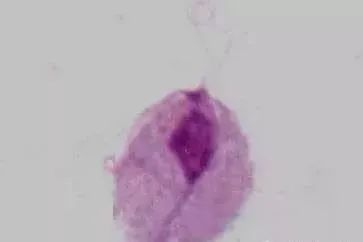

07 阴道毛滴虫

生理情况下,阴道 pH 为 4 ~ 4.5,不适宜阴道毛滴虫生存 (其最适 pH 为 5.5 ~ 6.0),故不引起女性生殖道滴虫性阴道炎。

病理情况下,滴虫可寄生于阴道后穹隆,常引起滴虫性阴道炎,可合并邻近器官的感染,如尿道和尿道旁腺感染。滴虫能利用上皮细胞内糖原作为能源进行直接分裂,主要传播途径是通过衣物和性交。

男性中,滴虫可寄生于包皮下、前后尿道、前列腺 (最多见,占 90%)、精囊内,可长时间持续存在,具感染性,经直接或间接方法传播。阴道毛滴虫感染的发病率,在男性可达 2% ~ 15%,女性则达 10% ~ 25%。男性常为携带者。滴虫也引起泌尿道症状和不孕症。